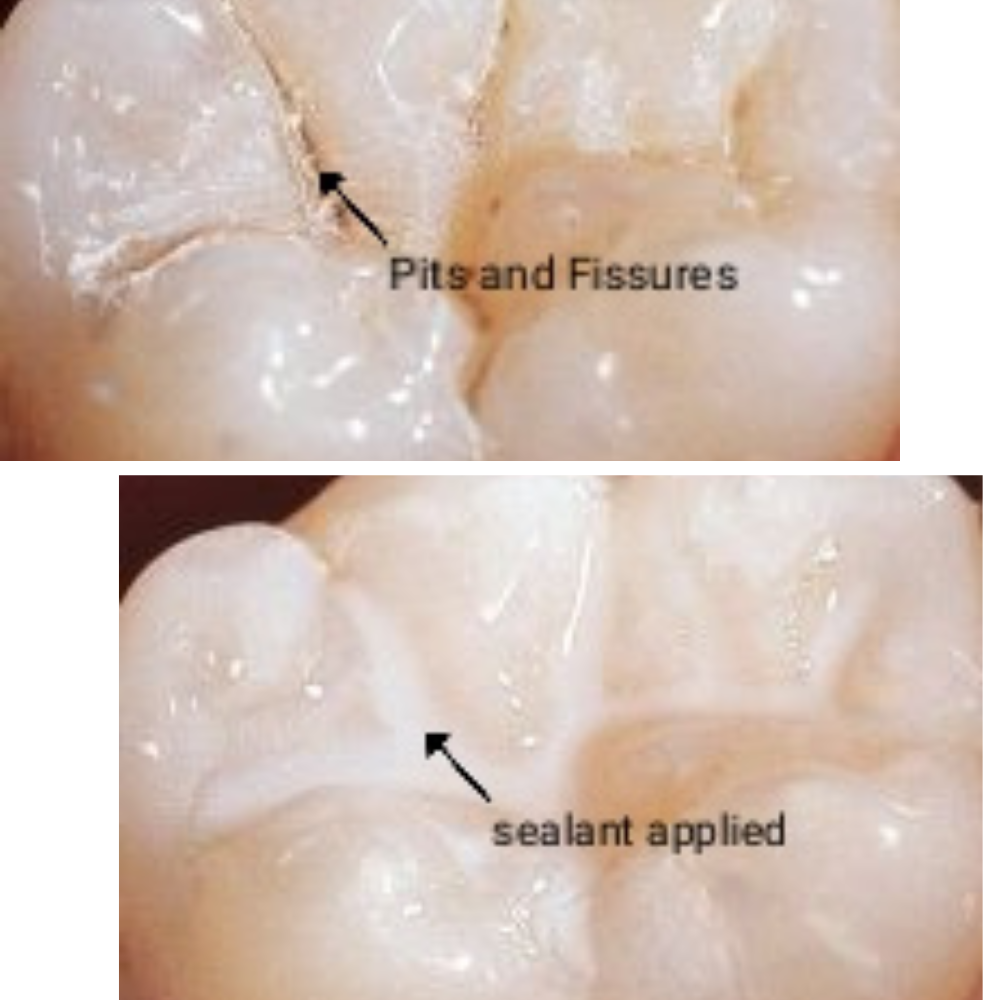

Pit and Fissure Sealants

Our clinic offers pit and fissure sealant treatments to protect teeth from cavities. A thin protective coating seals deep grooves, preventing food and bacteria buildup while keeping your teeth strong and healthy.